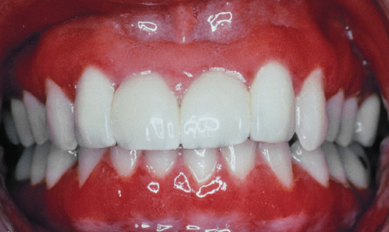

What is the likely diagnosis?

Plasma cell gingivitis.